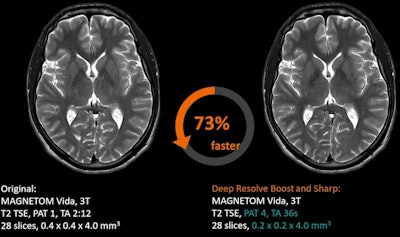

Deep Resolve Boost for MRI reconstructions, Siemens Healthineers

Deep Resolve Boost is a k-space-based reconstruction protocol that focuses on artifact reduction. It is a recent addition to the Deep Resolve AI-based reconstruction protocol for MRI, which was first introduced at RSNA 2020.

The software is available on the Magnetom Vida MRI scanner.Deep Resolve Boost enables users to acquire MRI exams with shorter time periods, such as a 15-second knee exam, with images then boosted to full image quality using the protocol, according to Siemens. Another protocol, Deep Resolve Swift Brain, enables a brain scan to be performed in less than two minutes.

Deep Resolve Boost is applicable from head to toe, and the "denoising strength" can be adapted by choosing from three levels. It can be combined with Deep Resolve Sharp and SMS TSE, rendering this the first k-space-to-image-space deep learning reconstruction that can be combined with simultaneous multi-slice turbo spin echo (TSE) imaging, the vendor claims.

"Image quality in standard 2D MRI sequences, accelerated in simulation beyond the threshold of standard acceptable noise levels, can be substantially improved by applying an iterative denoising algorithm using supplementary information about the image noise level," stated Dr. Johan Dehem, from Jan Yperman Ziekenhuis, Ypres, Belgium, in a Siemens-supported article about initial clinical experiences of the technology.

The software is available on the Magnetom Lumina, Magnetom Vida, Magnetom Vida Fit, Magnetom Altea, Magnetom Sola, and Magnetom Sola Fit. The minimum software version required is the Syngo MR XA50A and Syngo MR XA51A. Additional technical prerequisites may apply, stated the vendor.